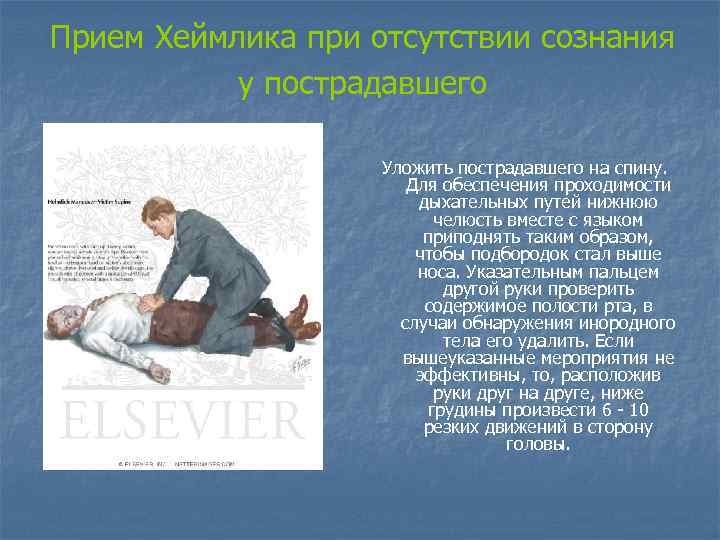

Прием Хеймлика при отсутствии сознания у пострадавшего Уложить пострадавшего на спину. Для обеспечения проходимости дыхательных путей нижнюю челюсть вместе с языком приподнять таким образом, чтобы подбородок стал выше носа. Указательным пальцем другой руки проверить содержимое полости рта, в случаи обнаружения инородного тела его удалить. Если вышеуказанные мероприятия не эффективны, то, расположив руки друг на друге, ниже грудины произвести 6 - 10 резких движений в сторону головы.